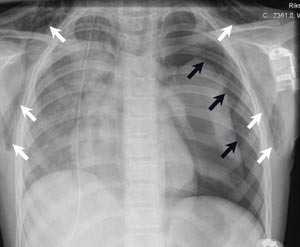

Første postoperative dag fikk pasienten 100 % oksygen via puritanfukter og kontinuerlig inhalasjon med racemisk adrenalin. Hun hadde perifer oksygenmetning på 95 – 100 %. Det subkutane emfysemet gikk betydelig tilbake. Røntgen thorax andre postoperative dag viste tilkommet atelektase apikalt på høyre lunge og fortetning basalt i venstre lunge. Pasientens kliniske tilstand bedret seg imidlertid gradvis og røntgenforandringene forsvant i løpet av 3 – 4 dager. Thoraxdrenene kunne fjernes fjerde postoperative dag og pasienten kunne utskrives fra sykehuset sjette dag etter operasjonen. Røntgen thorax viste da normalisering av de tidligere påviste forandringene (fig 3).